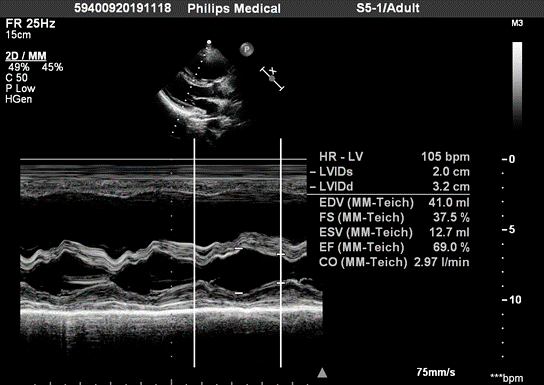

出院前复查心脏彩超示肺动脉高压消失69急性肺栓塞是院内猝死的主要

图片尺寸1080x1440